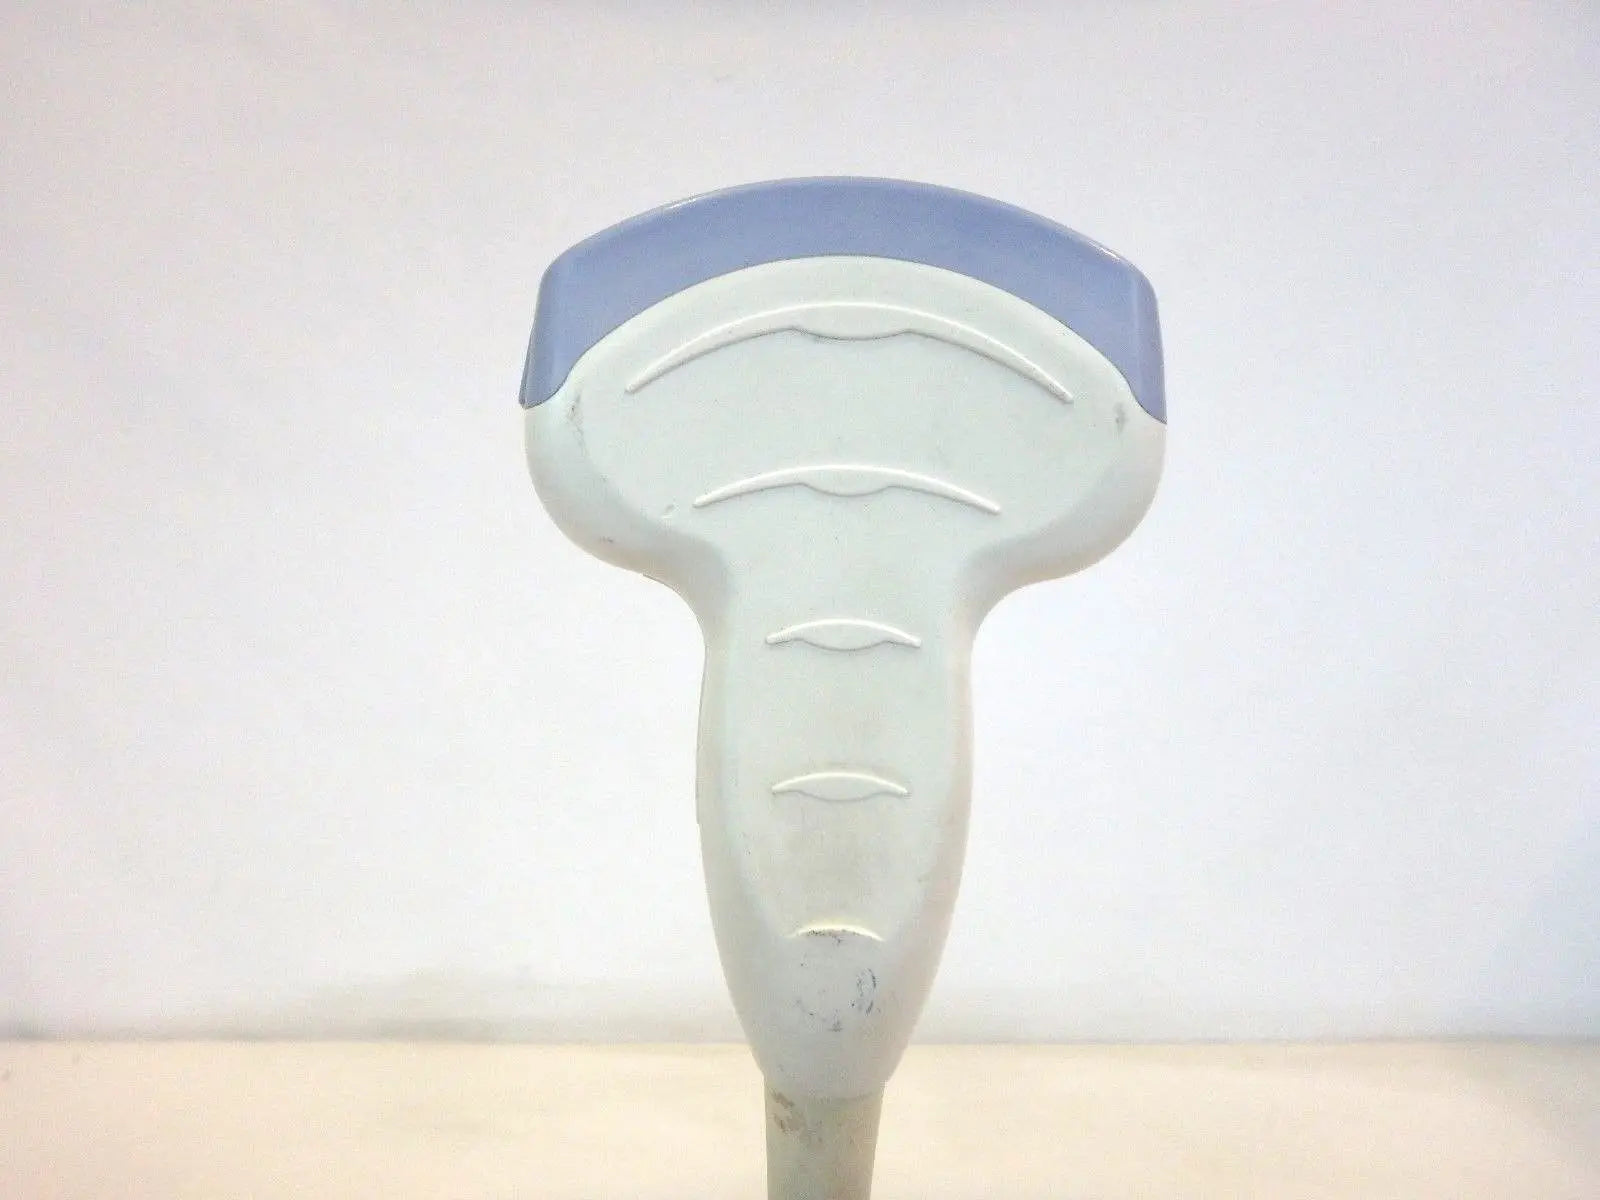

Seller Notes:âTested using a Logiq P5 Ultrasound unit. Plugs into ultrasound and produces image. Image has dead zones and white bars inconsistent with other functional transducers (pictured). Show signs of use. Includes everything shown. Sold AS IS.â

Brand: GE

Model: 4C